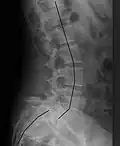

X-ray of the lateral lumbar spine with a grade III anterolisthesis at the L5-S1 level